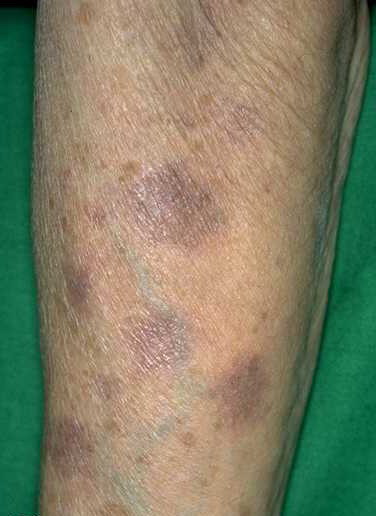

FDEs usually appear as solitary, erythematous, bright red or dusky red macules that may evolve into an edematous plaque; bullous-type lesions may be present. FDEs are most commonly found on the genitalia and in the perianal area, although they can occur anywhere on the skin surface . Some patients may complain of burning or stinging, and others may have fever,

malaise, and abdominal symptoms. FDE can develop from 30 minutes to 8 to 16 hours after ingestion of the medication. After the initial acute phase lasting days to weeks, residual grayish or slate-colored hyperpigmentation develops. On rechallenge, not only do the lesions recur in the same location, but also new lesions often appear.